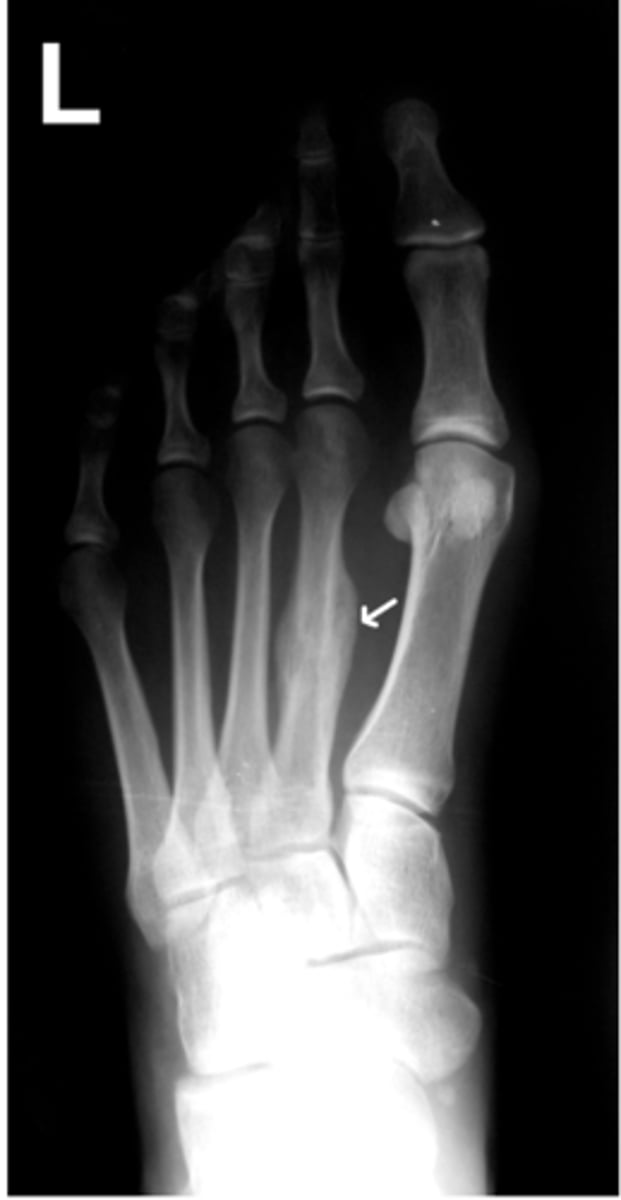

Disruption in the continuity of a bone:

Causes: High compression, tension, shearing, bending, or torsion forces

fractures

Further classified by:

- Open or closed

- Location

- Type or pattern of fracture line

X-ray confirms diagnosis, directs treatment